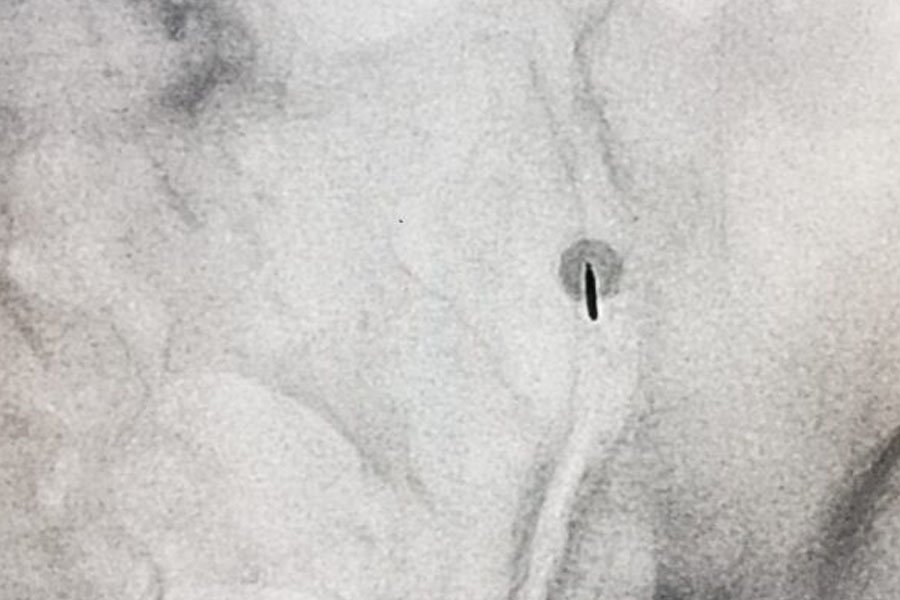

Nei casi resistenti a fisioterapia e terapia farmacologica, si ricorre a infiltrazioni periarticolari con cortisonici a lento rilascio, eseguite sotto guida ecografica o fluoroscopica per garantire precisione e sicurezza.

Infiltrazione dell’articolazione sacroiliaca